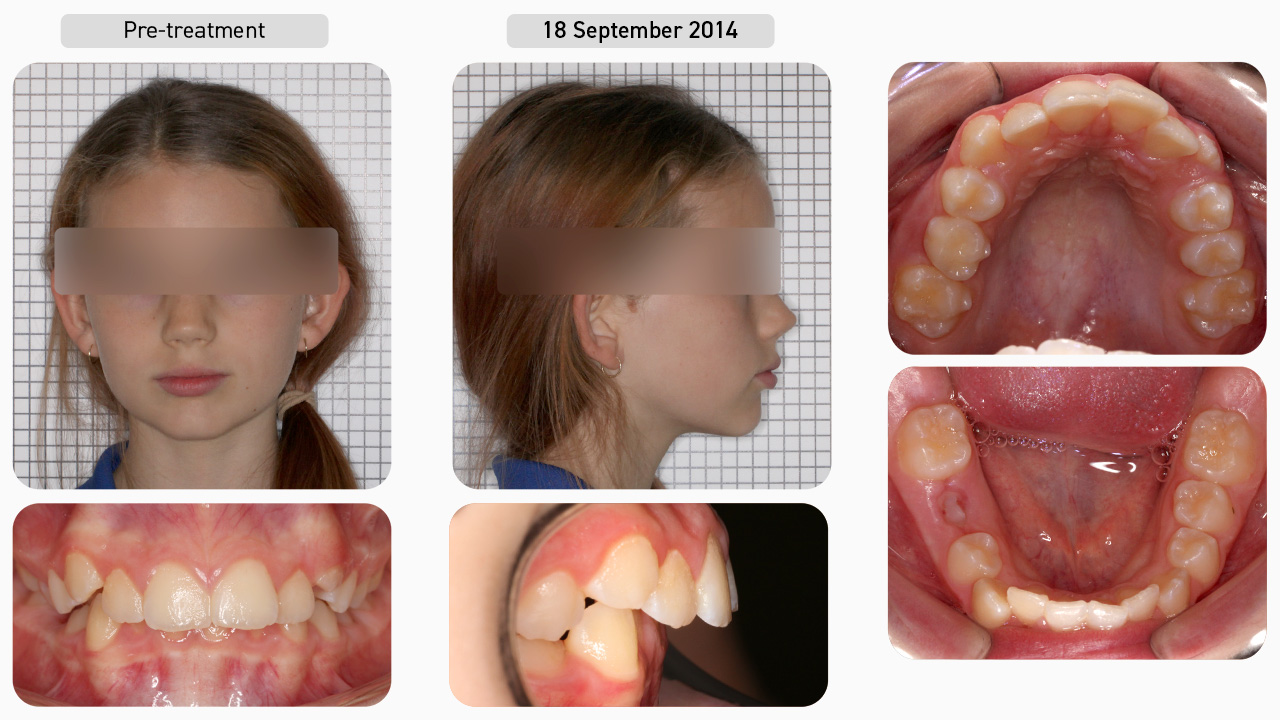

Case Study 1

This 11-year-old female patient presented with the chief complaint of crowded teeth and wanting to avoid braces. After being presented with the various treatment options, the decision was made to undertake Myobrace® treatment. This involved the use of a series of Myobrace® appliances in conjunction with the BWS arch expansion appliance and Myobrace® Activities.

Pre-treatment

Conducting a Myofunctional Orthodontic Evaluation (MOE), we documented that this patient had moderate dental crowding with narrow and flattened arches, as well as a retruded mandible. There was also a deep overbite and moderate overjet. Her poor habits included mouth breathing with low tongue posture and a severe reverse swallow. She also had a history of thumb sucking as a child. Since she was in the developing permanent dentition, this patient was suited to the Myobrace®for Teens series.

Dental Progression

She started with the T1 appliance to establish nasal breathing and begin the correction of myofunctional habits. Two months later, her breathing function had improved, and she was consistently retaining the T1 overnight, so she progressed onto the T2 appliance to focus on arch development and continued habit correction. Since the patient was above the age of eight, the decision was made to use the BWS for extra arch development. Note that despite the overjet, we still developed the upper arch as the focus at this stage is on improving room for the tongue, not focused on the teeth. The BWS must be combined with a first stage appliance, so the T1 was reissued to the patient.

Dental Progression

The BWS generally requires four months of expansion, but due to rapid progress, only two months of expansion was needed. The wire was then removed and the patient was reissued the T2 appliance. A few months later, the patient was issued the T3 appliance for further dental alignment. As the upper arch was still slightly underdeveloped, the decision was made to enter a second round of BWS expansion to develop the upper arch and create more space for the tongue and the upper left canine. With the BWS back in, the patient was issued the T1BWS appliance, which is the preferred appliance to use with the BWS.

Dental Progression

Following the second round of BWS expansion, the patient was reissued the T2 appliance. Once the arches were nicely developed and her habits largely corrected, the patient was moved on to the T3 appliance for further dental alignment and, finally, the T4 appliance for retention.

Treatment Complete

This patient had less than two years of treatment. Once the goals of Myobrace® treatment had been achieved (correction of breathing and myofunctional habits, arch form and dental alignment), the patient entered into the retention phase. The T4 appliance was issued to retain the arch form, alignment and habits, allowing her to continue to develop correctly into the future.

Facial Progression

Once breathing and myofunctional disorders have been corrected, the development of the face continues in the correct downward and forward direction. The mandible has moved forward, which has positive effects on the breathing patterns, while the labiomental crease has shallowed as a result of correcting swallowing function.

Treatment Summary

Using the Myobrace® appliances in conjunction with BWS arch expansion and the Myobrace® Activities, we have helped the patient to establish nasal breathing, correct her myofunctional habits and, therefore, achieve natural alignment of the teeth. In Myobrace® treatment, we are not concerned with dental ‘perfection’ as we are looking for natural alignment, occurring with habit correction. With the correct breathing and myofunctional habits maintained, we can expect further improvements in the teeth and jaws as the patient continues to develop. For example, note that the overjet reduced further even after treatment was complete, as can be seen in the one-and-a-half-year retention photos.

Retention

The patient returned for a retention check appointment approximately one and a half years after treatment was complete and the result has been maintained without the use of any fixed retainers. The arches are broad and round, the deep bite has opened up and the overjet has reduced. With the correct breathing and muscle habits continued, we expect this stability to be maintained.